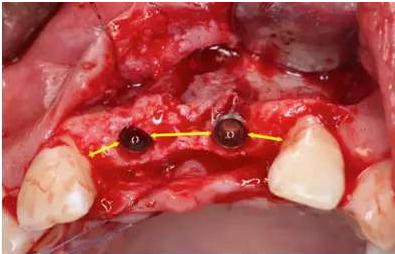

做牙槽嵴頂切口及22牙遠(yuǎn)中附加切口,翻瓣;

在11、21位置植入兩顆NobelActive 3.5mm*13mm種植體;

分析種植體植入三維位置,包括:

1. 近遠(yuǎn)中位置:理想修復(fù)體近遠(yuǎn)中中點(diǎn),與鄰牙牙根余留1.5mm間隙,種植體間間隔3mm以上。

2. 唇舌向位置:稍偏舌側(cè)

3. 冠根向位置:種植體平臺(tái)位于理想齦緣最高根方3mm處。

種植體頰側(cè)骨缺損處植入Bio-Oss骨替代品